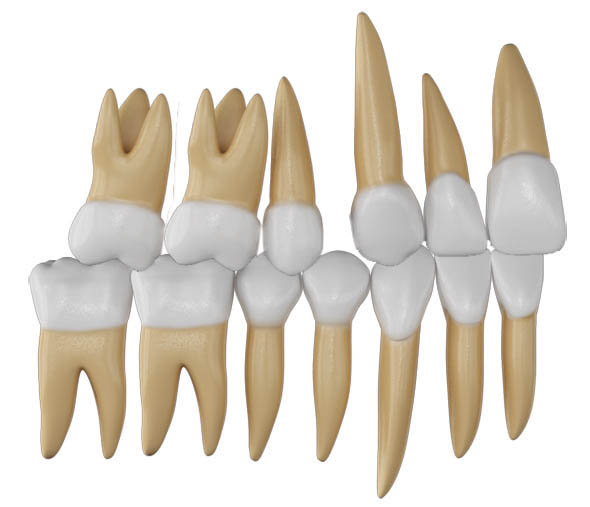

شکل 25-2: رابطه مولری بخاطر کشیدن پرمولرهای بالا یک کاسپ کامل کلاسII تمام میشود

شکل 26-2: یک کاسپ کامل کلاسII